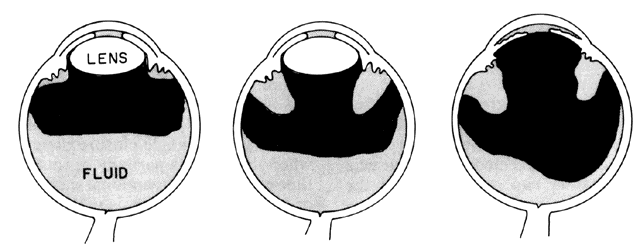

There are several classifications that have been developed in an attempt to identify those patients at risk for angle closure. Van Herick15 developed a slit lamp grading system based on the depth of the peripheral anterior chamber as measured by the adjacent corneal thickness seen in the slit lamp beam directed at the limbus. In van Herick's system, a grade 1 depth is the narrowest and a grade 4 depth is a deep anterior chamber. When a grade 1 or 2 depth is present, that is, peripheral anterior chamber depth less than one half corneal thickness, gonioscopy should be performed to rule out occludable angles. Scheie's23 grading system is based on the depth of angle structures visible on gonioscopy with a grade IV angle being narrow and visible only to Schwalbe's line. Shaffer developed the following classification for describing angle width and the likelihood of angle closure. If an angle recess width is 20 degrees or more, angle closure is improbable (Fig. 1). Angles between 10 and 20 degrees have an increased risk of developing angle closure (Fig. 2). Below 10 degrees, angle closure is probable or actually present (Figs. 3 and 4).24 When evaluating an angle, however, it is also necessary to consider the peripheral iris configuration and iris root insertion.25 Spaeth developed a gonioscopic classification system based on three elements: (1) the angle width in degrees; (2) the configuration of the peripheral iris; and (3) the insertion of the iris root.26

Fig. 1. Anterior chamber angle width. Cross-sectional diagram of a deep anterior chamber with a nearly flat iris plane, minimal apposition between the iris and lens at the pupil, and a wide-open angle entrance to the filtration area. In this type of eye, aqueous passes easily from the posterior chamber through the pupil into the anterior chamber and out through the filtration area. (Kolker AE, Hetherington J Jr: Becker and Shaffer's Diagnosis and Therapy of the Glaucomas, p 42. St. Louis, CT Mosby, 1970)

Fig. 2. Anterior chamber angle width. A Shallow anterior chamber with a more anteriorly located lens than is shown in Figure 1. Apposition of the lens and iris in the pupillary zone is increased, producing a relative pupillary block that interferes with aqueous flow from the posterior to the anterior chamber. The pressure differential between the posterior and anterior chambers is increased. (Kolker AE, Hetherington J Jr: Becker and Shaffer's Diagnosis and Therapy of the Glaucomas, P 42. St. Louis, CV Mosby, 1970)

Fig. 3. Anterior chamber angle width. Extremely narrow anterior chamber angle entrance with a mid-dilated pupil and a lax peripheral iris. Increased pressure in the posterior chamber pushes the peripheral iris forward where it lies near the filtration area; at this stage, it does not block outflow of aqueous or increase intraocular pressure. (Kolker AE, Hetherington J Jr: Becker and Shaffer's Diagnosis and Therapy of the Glaucomas, p 43. St. Louis, CV Mosby, 1970)

Fig. 4. Anterior chamber angle width. The angle has closed and the iris now lies against the trabecular meshwork, obstructing outflow. If closure has occurred around a significant portion of the circumference of the angle, intraocular pressure will rise. (Kolker AE, Hetherington J Jr: Becker and Shaffer's Diagnosis and Therapy of the Glaucomas, p 43. St. Louis, CV Mosby, 1970)